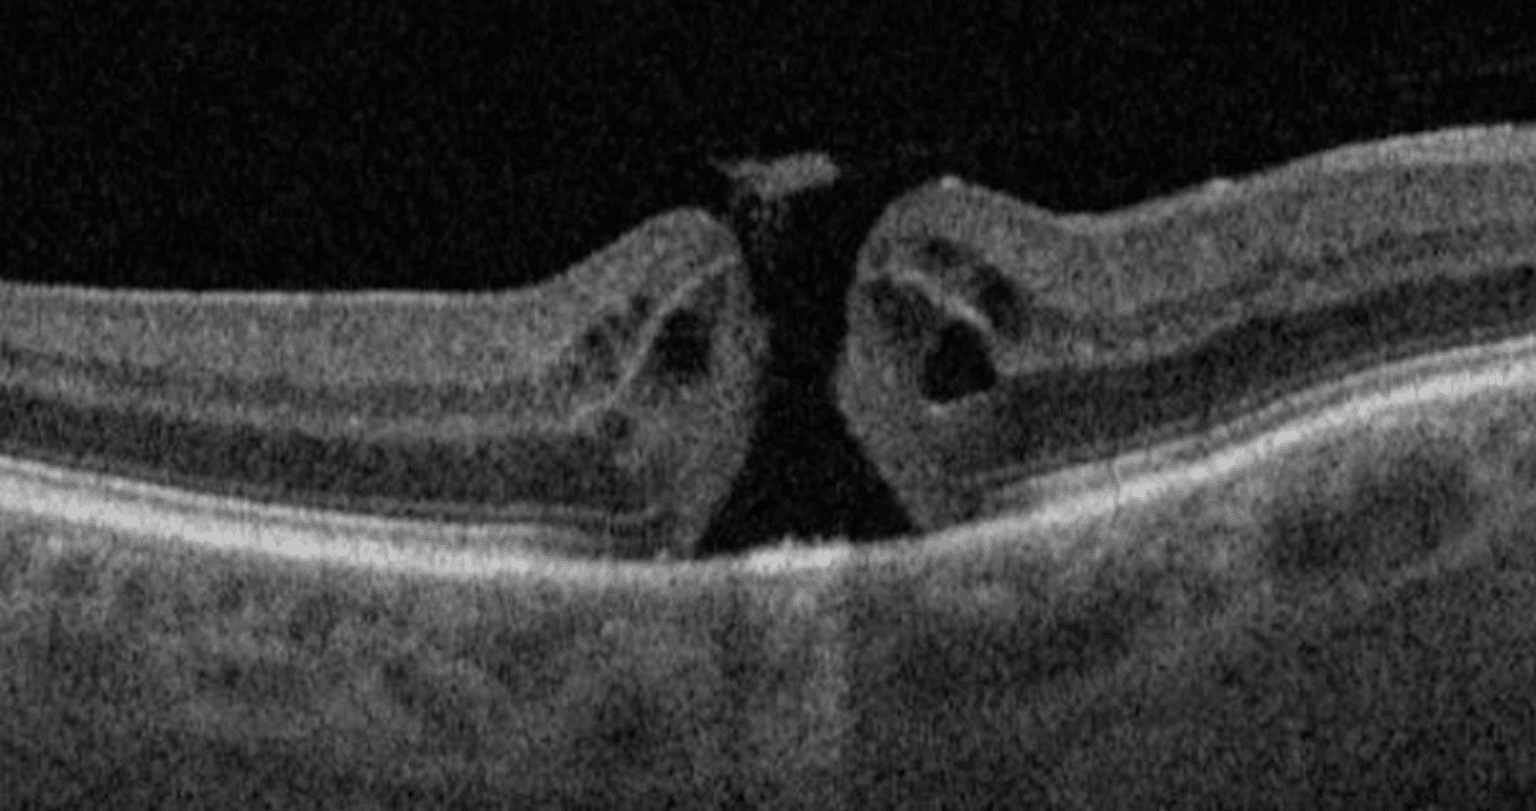

Vitreomacular Traction I Mr Ellabban Eye Surgery Yorkshire & Hull Laser Eye Surgery Yorkshire Clinic outstanding personalised laser eye surgery, lens replacement and dry eye treatment in leeds and york. Lasik is the most popular type of laser eye surgery. Laser eye surgery, cataract surgery and lens replacement are easily accessible from our yorkshire eye hospital. visit eye clinic near you in yorkshire and get your vision corrected by accuvision. With over 20. Laser Eye Surgery Yorkshire Clinic.